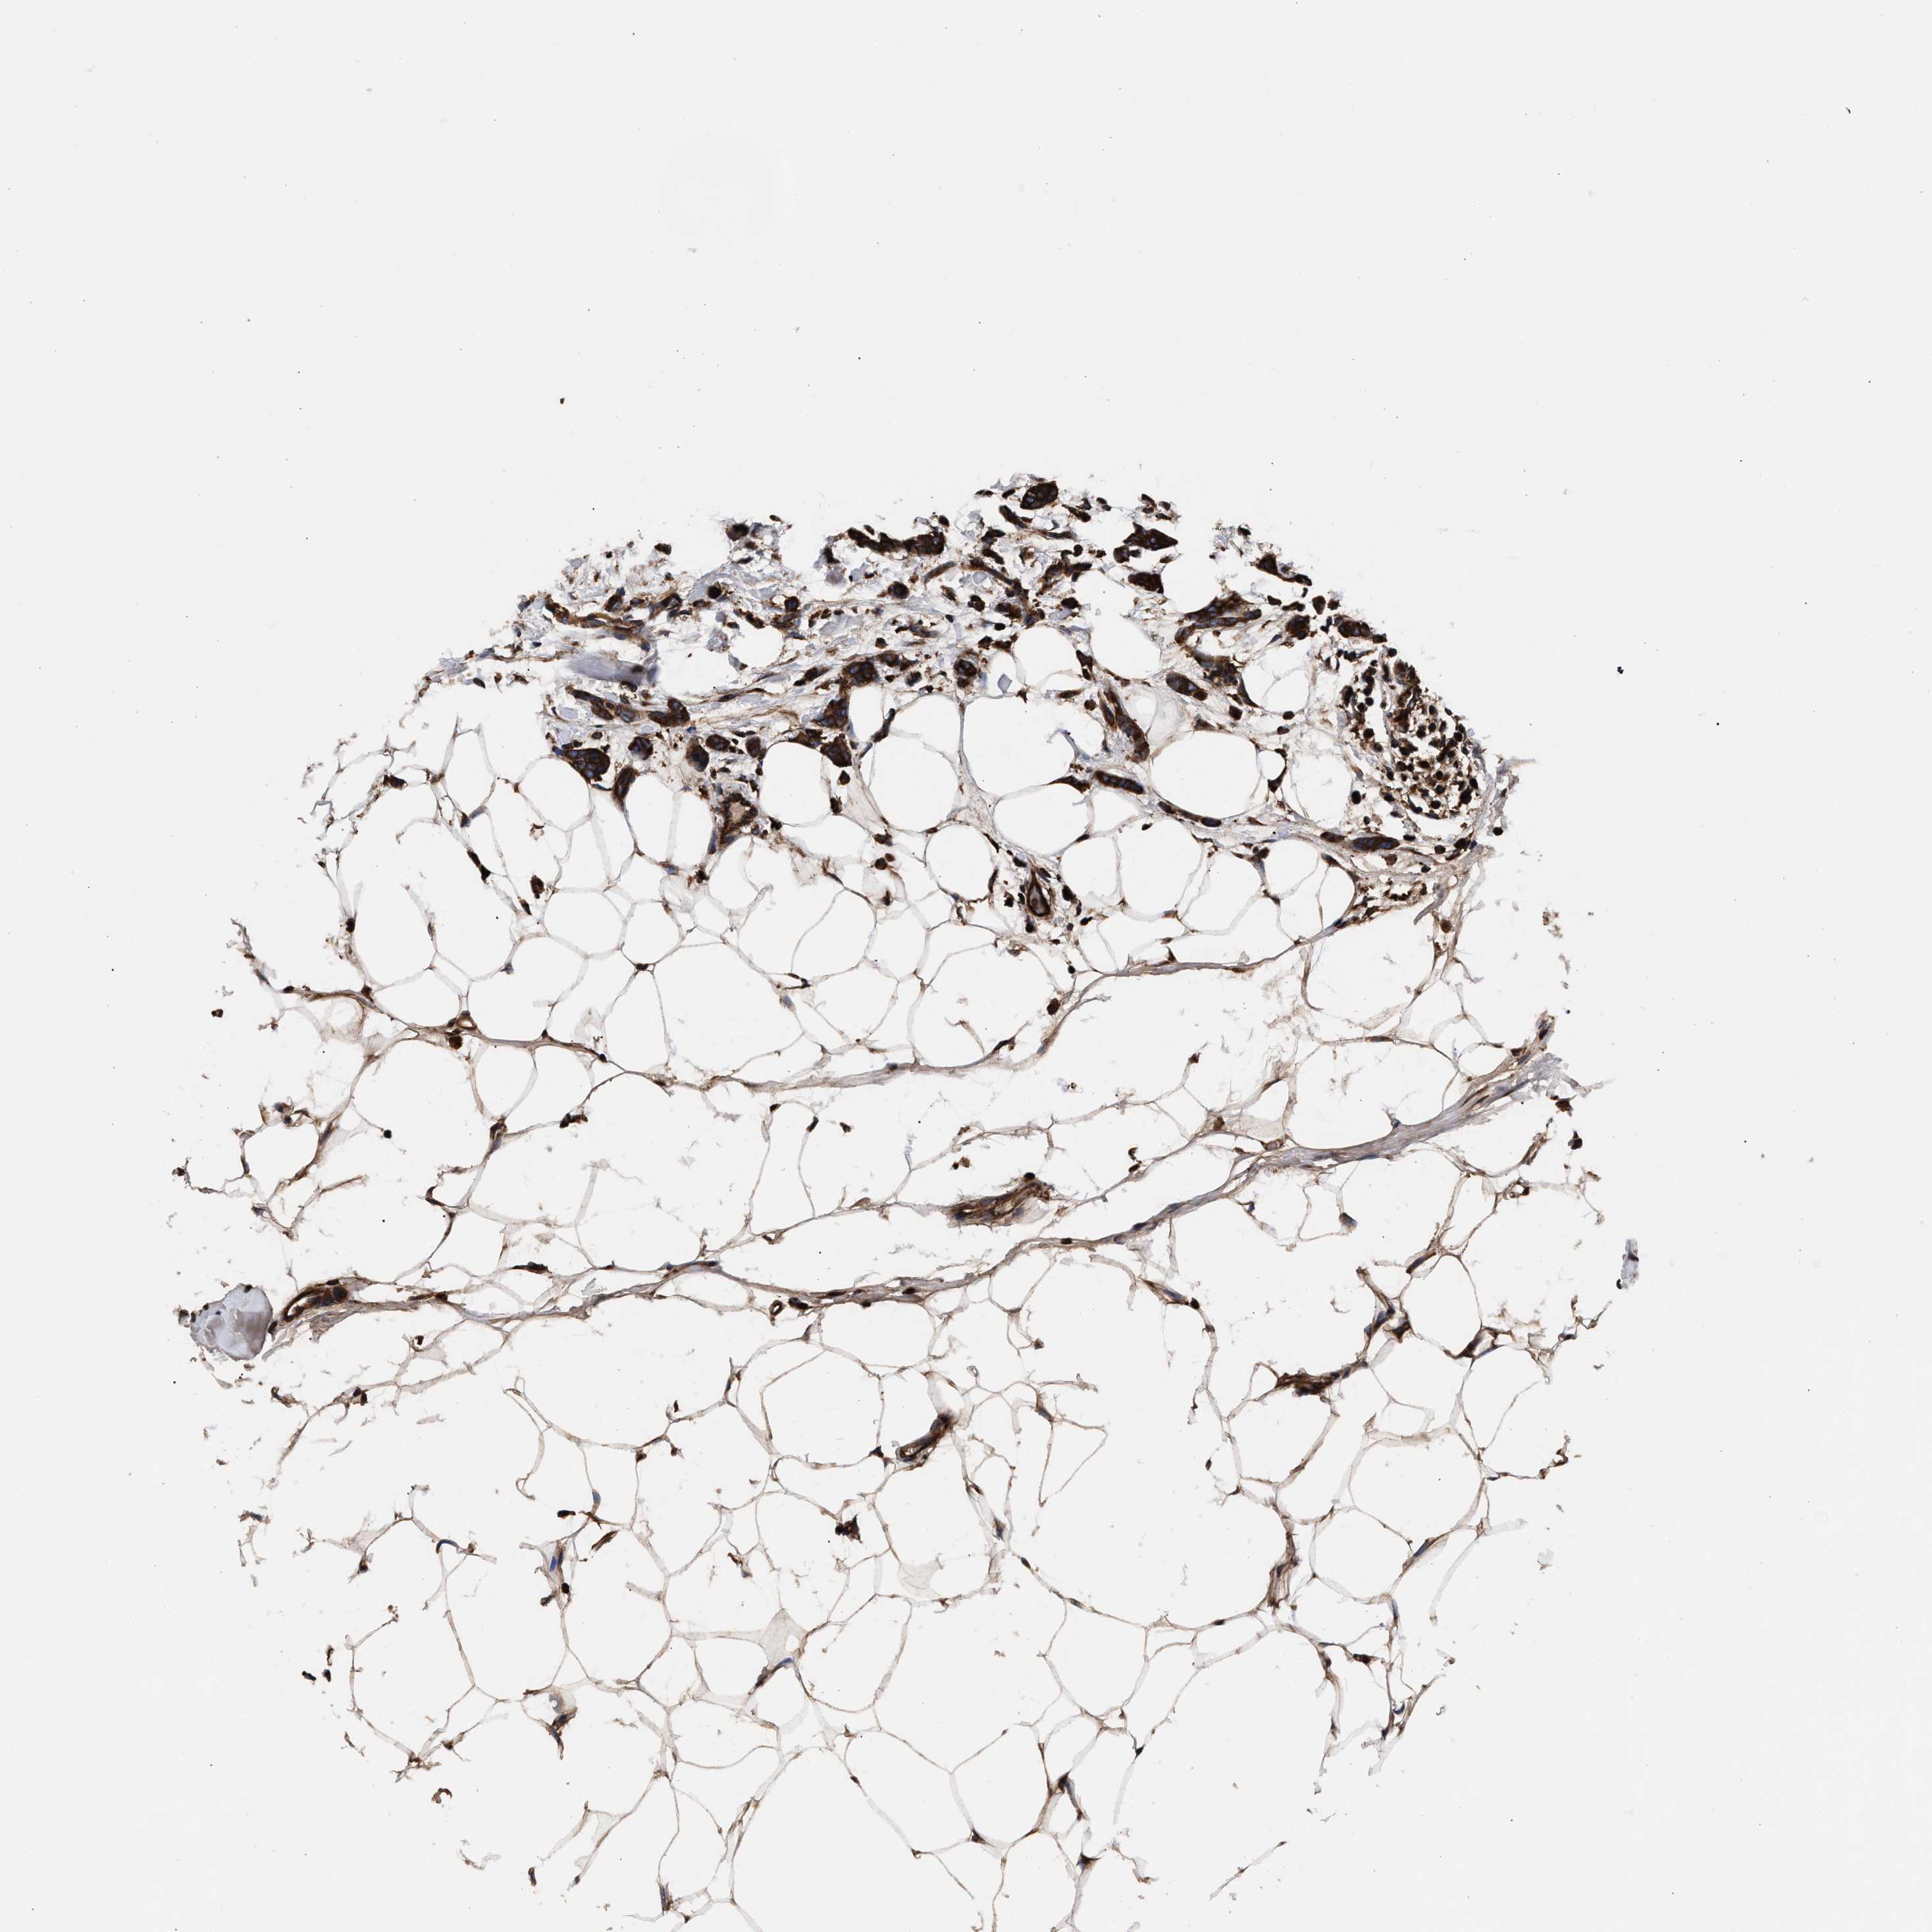

BRCA TCGA BRCA VALIDATION PROTEIN EXPRESSION

ANTIBODIES

AND

VALIDATION